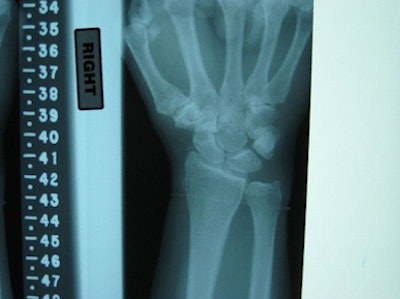

![]() |

| The two clinical images show the difference in a plain radiograph (above) and fluoroscopic image (below) of the same wrist and the modalities' ability to show the scapholunate interval. |